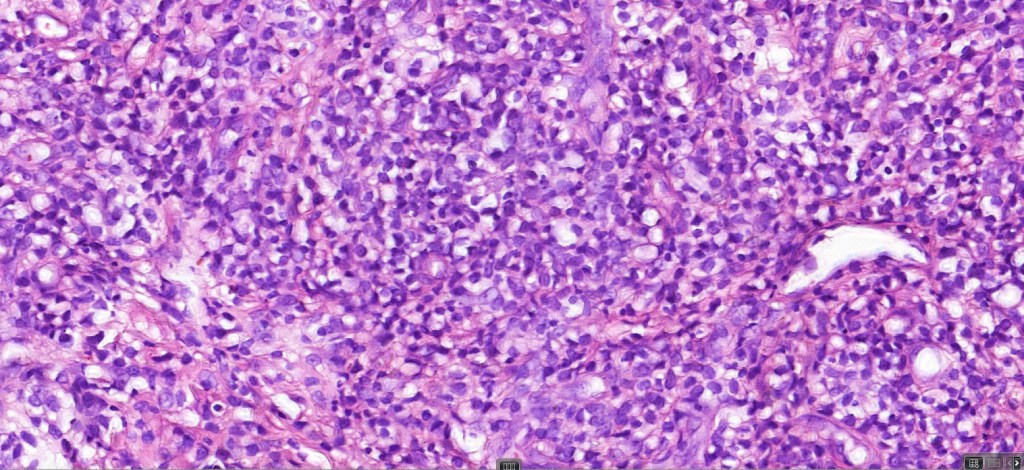

Histological features

The histological hallmark of mycosis fungoides is the presence of large atypical lymphocytes with a convoluted/cerebriform nuclear border (Sézary cells). These may be found at the epidermal-dermal jnuction and as collections within the epidermis (Pautrier microabscess). These are most easily found in plaque stage disease. The epidermal component can be subtle in patch stage disease and is often lost in tumor stage dsease. The classification into patch, plaque & tumor stage disease is less helpful histologically as the features merge from one to the other. It is all a matter of degree.

Tumor Stage Disease

•Epidermotropism is often minimal or absent

•Dense, broad diffuse or nodular, dermal infiltrate often extending into the subcutaneous fat

•Abundant Sézary cells. Frequently accompanied by very pleomorphic forms

•Mitoses often abundant, frequently abnormal

•CD30 expression correlates with transformation (cells X4 size of small lymphocytes comprising 25% or more of the infiltrate or the presence of a distinct large nodule)